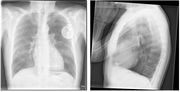

| 20:14, 5 August 2012 | Xthorax.jpg (file) |  |

44 KB | 1 | |